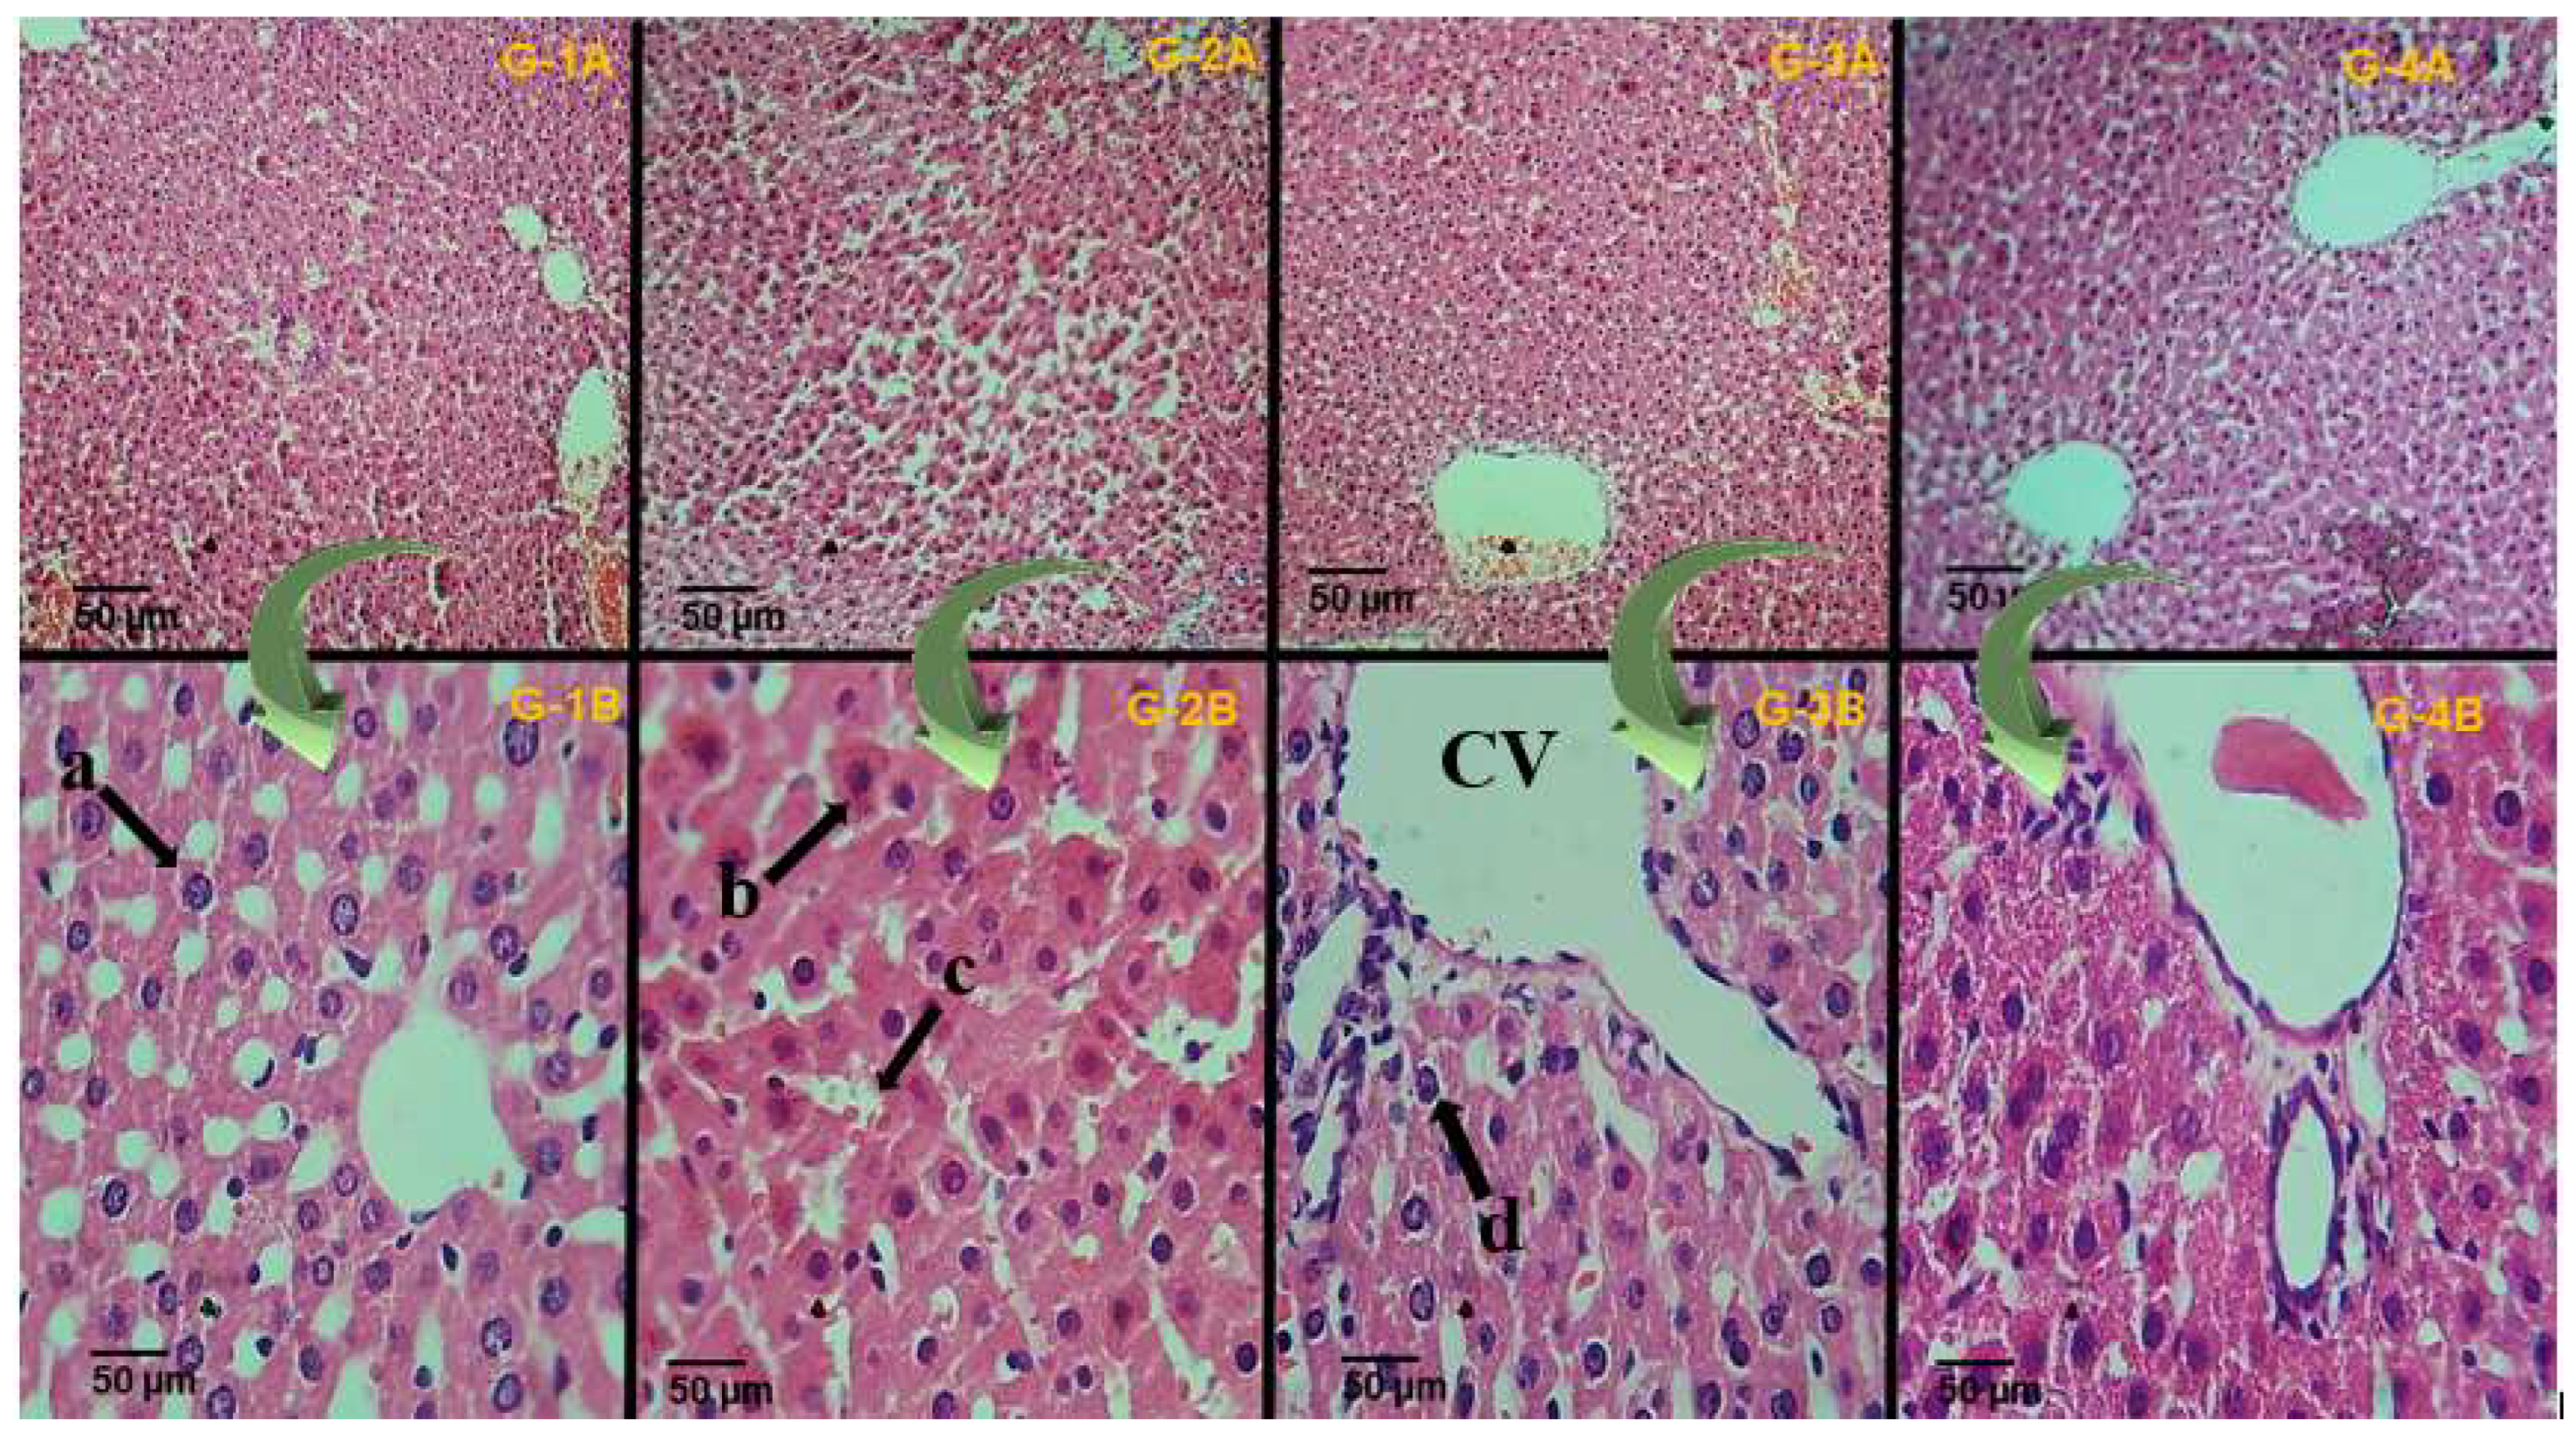

The histological examination of liver tissues (seen both in Figure 8 and in Table 6) revealed that the nicotine intoxication of rats significantly damaged the hepatic cells in the hepatic tissues (Figure 8(G-2B)) compared to the normal control group, as a normal hepatic cell is composed of mononuclear mature cells is seen with not any type of necrosis, apoptosis, and inflammation. As edema or liver damage is seen both in the intoxicated or positive control group compared to the plant-treated group in which there is mild inflammation, no edema is seen, and there was no necrosis (Figure 8(G-4B)). The administration of tricin (10 mg/kg body weight (b.w.)) and the positive controls exhibited significant improvement in the histo-architecture after nicotine intoxication (Figure 8(G3B,G4B)).

Figure 8.

Histological sections obtained from liver tissues of different experimental male rats after staining with an H & E stain (10× and 40×); grouping is the same column-wise. The only difference is in the picture magnification. (G-1A,G-1B): Normal control group; (G-2A,G-2B): Intoxicated group; (G-3A,G-3B): Positive control group; (G-4A,G-4B): Phytochemical (tricin) treated group. The letters (a–d) indicate different histological features of the liver, such as (a) representing the nucleus, (b) representing the inflammation, (c) representing necrosis, and (d) hepatocytes. (CV) central vein.